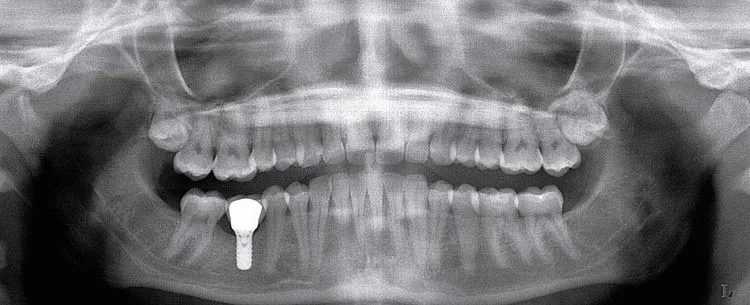

Did you know that without x-rays we might not find cavities or the beginnings of disease in your mouth? To avoid damaged or lost teeth, we use modern dental technology to take x-rays. This lets us discover problems before they become more serious.

Dental x-rays are very low in terms of the amount of radiation involved compared to other types of x-rays. With the latest dental technology, dental x-rays have become even safer than before. We know that the benefits of x-rays to your health are much greater than the small risk of radiation exposure.

To limit radiation exposure, we use a lead shield over your body when taking necessary x-rays. How often we take them depends on your age, risk for disease, and any symptoms of oral disease. Generally, children have more x-rays taken than adults because children’s’ teeth and jaws are still developing.

X-rays can reveal important issues invisible to the naked eye such as:

It’s crucial for us to catch these items early to save you time, cost, and discomfort. Without x-rays, we may not detect something significant about your teeth and health. Please speak with us if you have any concerns about x-rays.